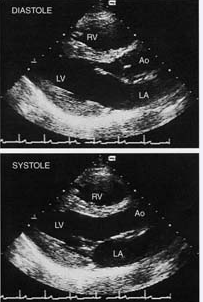

http://webres.medlive.cn/upload/000/020/101

胸骨旁左室长轴切面

Schematic diagram of the parasternal long-axis view in diastole

showing the aortic root (Ao), sinotubular junction (STJ), closed right coronary and noncoronary cusps of the aortic valve (RCC and NCC), the open anterior and posterior mitral valve leaflets (AMVL and PMVL), and the left ventricular septum and posterior wall. The medial papillary muscle has been shown for reference, although slight medial angulation is needed to visualize this structure in the long-axis view. The right ventricular outflow tract (RVOT) is anterior, while the coronary sinus (CS) in the atrioventricular groove and the descending aorta (DA) are seen posteriorly. The right pulmonary artery (RPA) lies posterior to the ascending aorta. The position of the pericardium is indicated by the thin line. Normal parasternal long-axis 2D echo images at end-diastole (above) and end-systole (below).